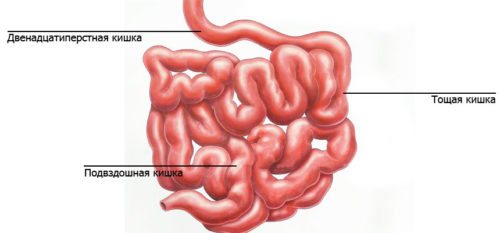

Робот Да Винчи позволяет проводить различные операции в разных областях медицины. Некоторые из них включают:

- Хирургия пищевода и желудка. Робот позволяет удалить опухоли или провести реконструкцию пищевода и желудка.